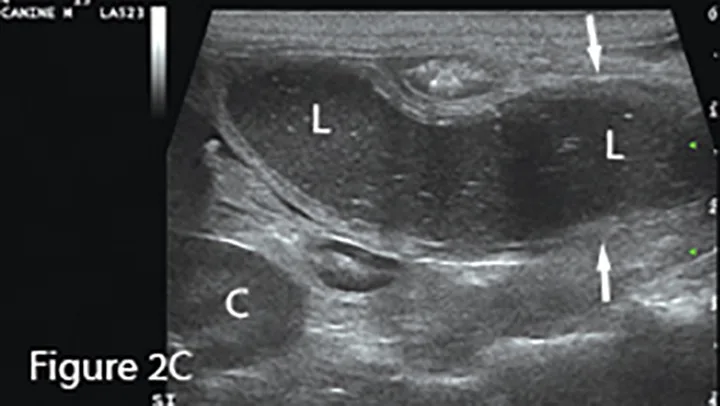

A longitudinal segment of severely fluid-distended small intestine (arrows) adjacent to normal bowel seen in transverse sections (*), suggesting obstruction. The greatly dilated lumen (L) shows speckled, echogenic fluid with readily observable movement in real-time examination. Potential cause (eg, foreign material, mass, intussusception) should be investigated. (K = caudal pole of kidney)

Focal loss of wall layering and eccentric thickening of the intestinal wall (arrows) are present on ultrasound image showing abnormally dilated small intestinal lumen (L) orad to the mass. Normal empty small intestinal segments are seen in the transverse section in the near field (*). Surgery confirmed diagnosis of mucinous adenocarcinoma.